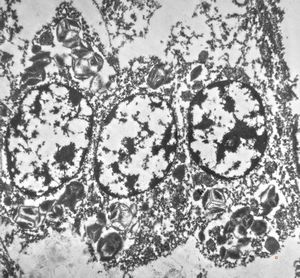

bone marrow - crystalloid inclusions Charcot-Leyden crystals formation

bone marrow - crystalloid inclusions Charcot-Leyden crystals formation v.s.